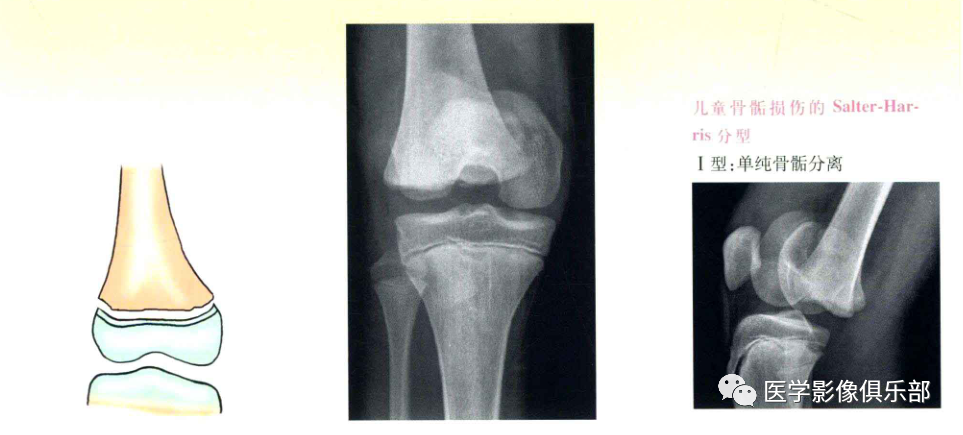

Salter-Harris分型

Ⅰ型:单纯骨骺分离;

Ⅰ、Ⅱ型损伤,骨折线不经过骨骺,通常不造成生长发育障碍,Ⅲ、Ⅳ型累及骨骺,可造成生长阻滞和进行性畸形。